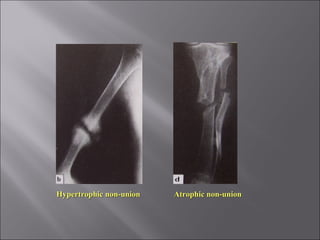

 Condition when the fracture will never unite w/o

intervention

 Healing has stopped.

Fracture gap is filled by fibrous tissue

 Clinical featuresClinical features

 Painless movement at the fracture site

 X-RayX-Ray

 Fracture is clearly visible

 Fracture ends are rounded, smooth and sclerotic

 Atrophic non-unionAtrophic non-union : - Bone looks inactive

(Bone ends are often tapered / rounded)

- Relatively avascular

Hypertrophic non-unionHypertrophic non-union : - Excessive bone formation

` - on the side of the gap

- Unable to bridge the gap

Hypertrophic non-unionHypertrophic non-union Atrophic non-unionAtrophic non-union